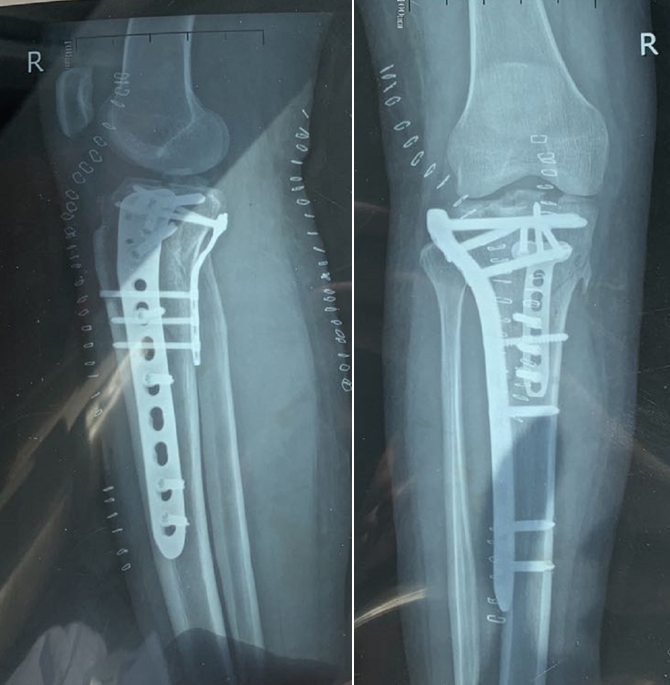

核磁检查后,C女士在玉门市中医医院接受了“右胫骨骨折内牢靠手术”治疗,并行“交织韧带重修手术”治疗。

▲患者影像学检查